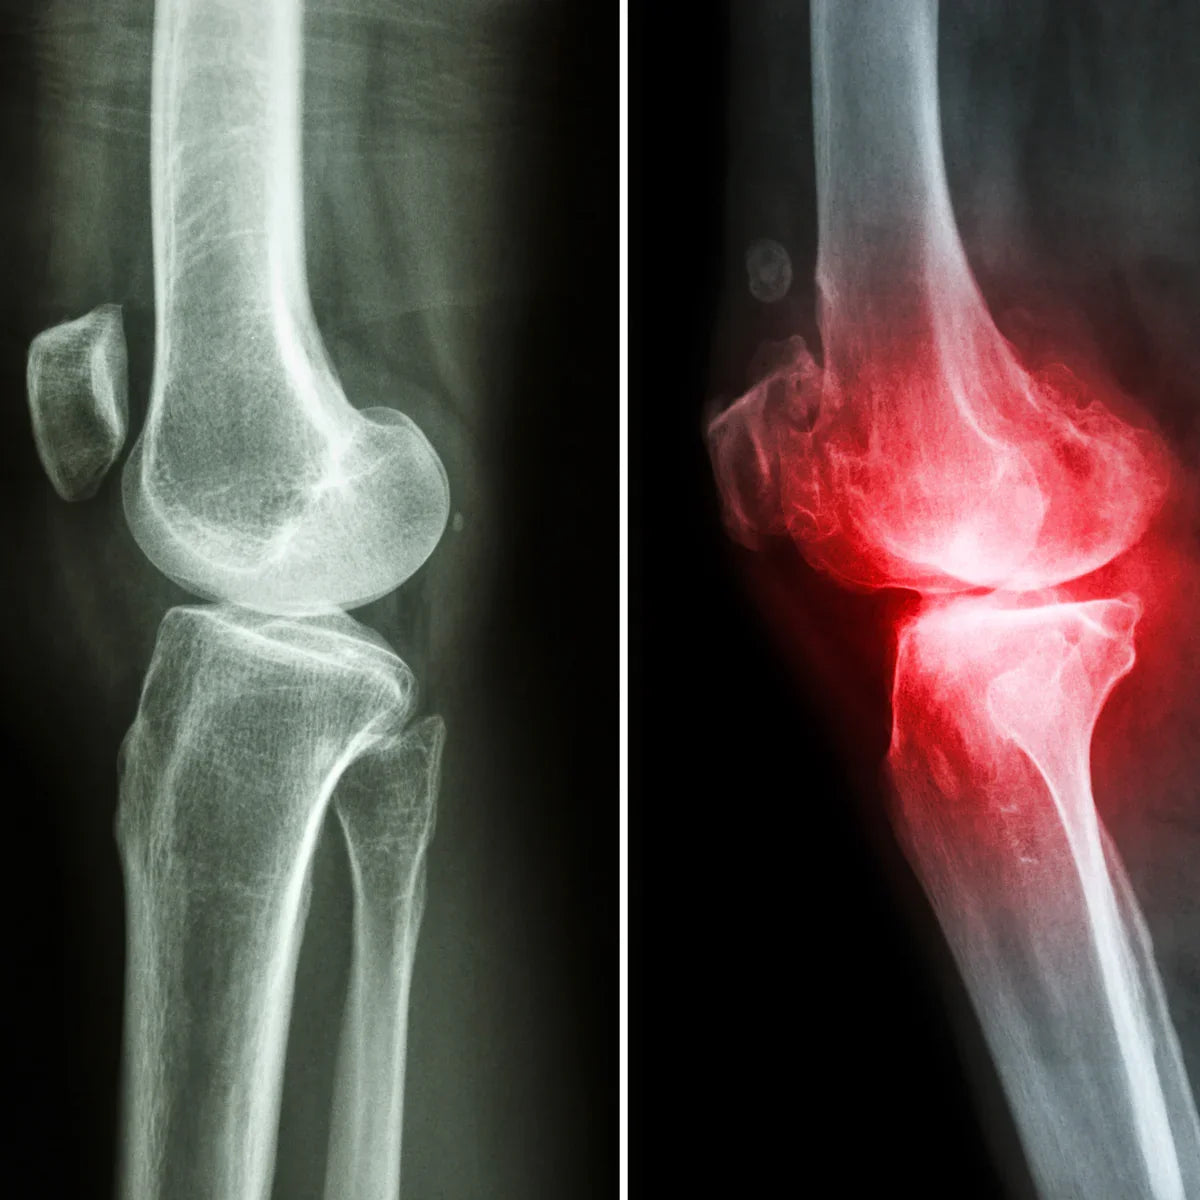

Mannaflex ajută la reducerea rigidității, inflamației și durerii cauzate de reumatism, restabilind astfel libertatea de mișcare.

- Inflamație articulară

- Rigiditate articulară stiffness

- Artrită reumatoidă

- Osteoartrită

- Durere musculară

- Durere articulară puternică

- Articulații rigide și mușchi

- Durere de spate

- Durere de genunchi

- Umflate, părți ale corpului edematoase